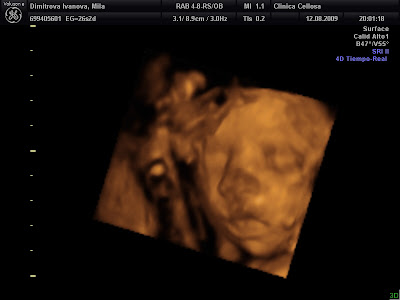

Emma en la tripita de Mila... qué preciosa... si se le ve la carita perfectamente!!

Pues para Noviembre esperamos a la pequeña Emma!! Qué ganas de verla ya!! :-P Pero que aguante ahí en la tripita porque lo de ser sietemesino no está bien visto!! Emma corazón, no tengas ninguna prisa por salir, que quiero ver a Milagritos gordita gordita :-P